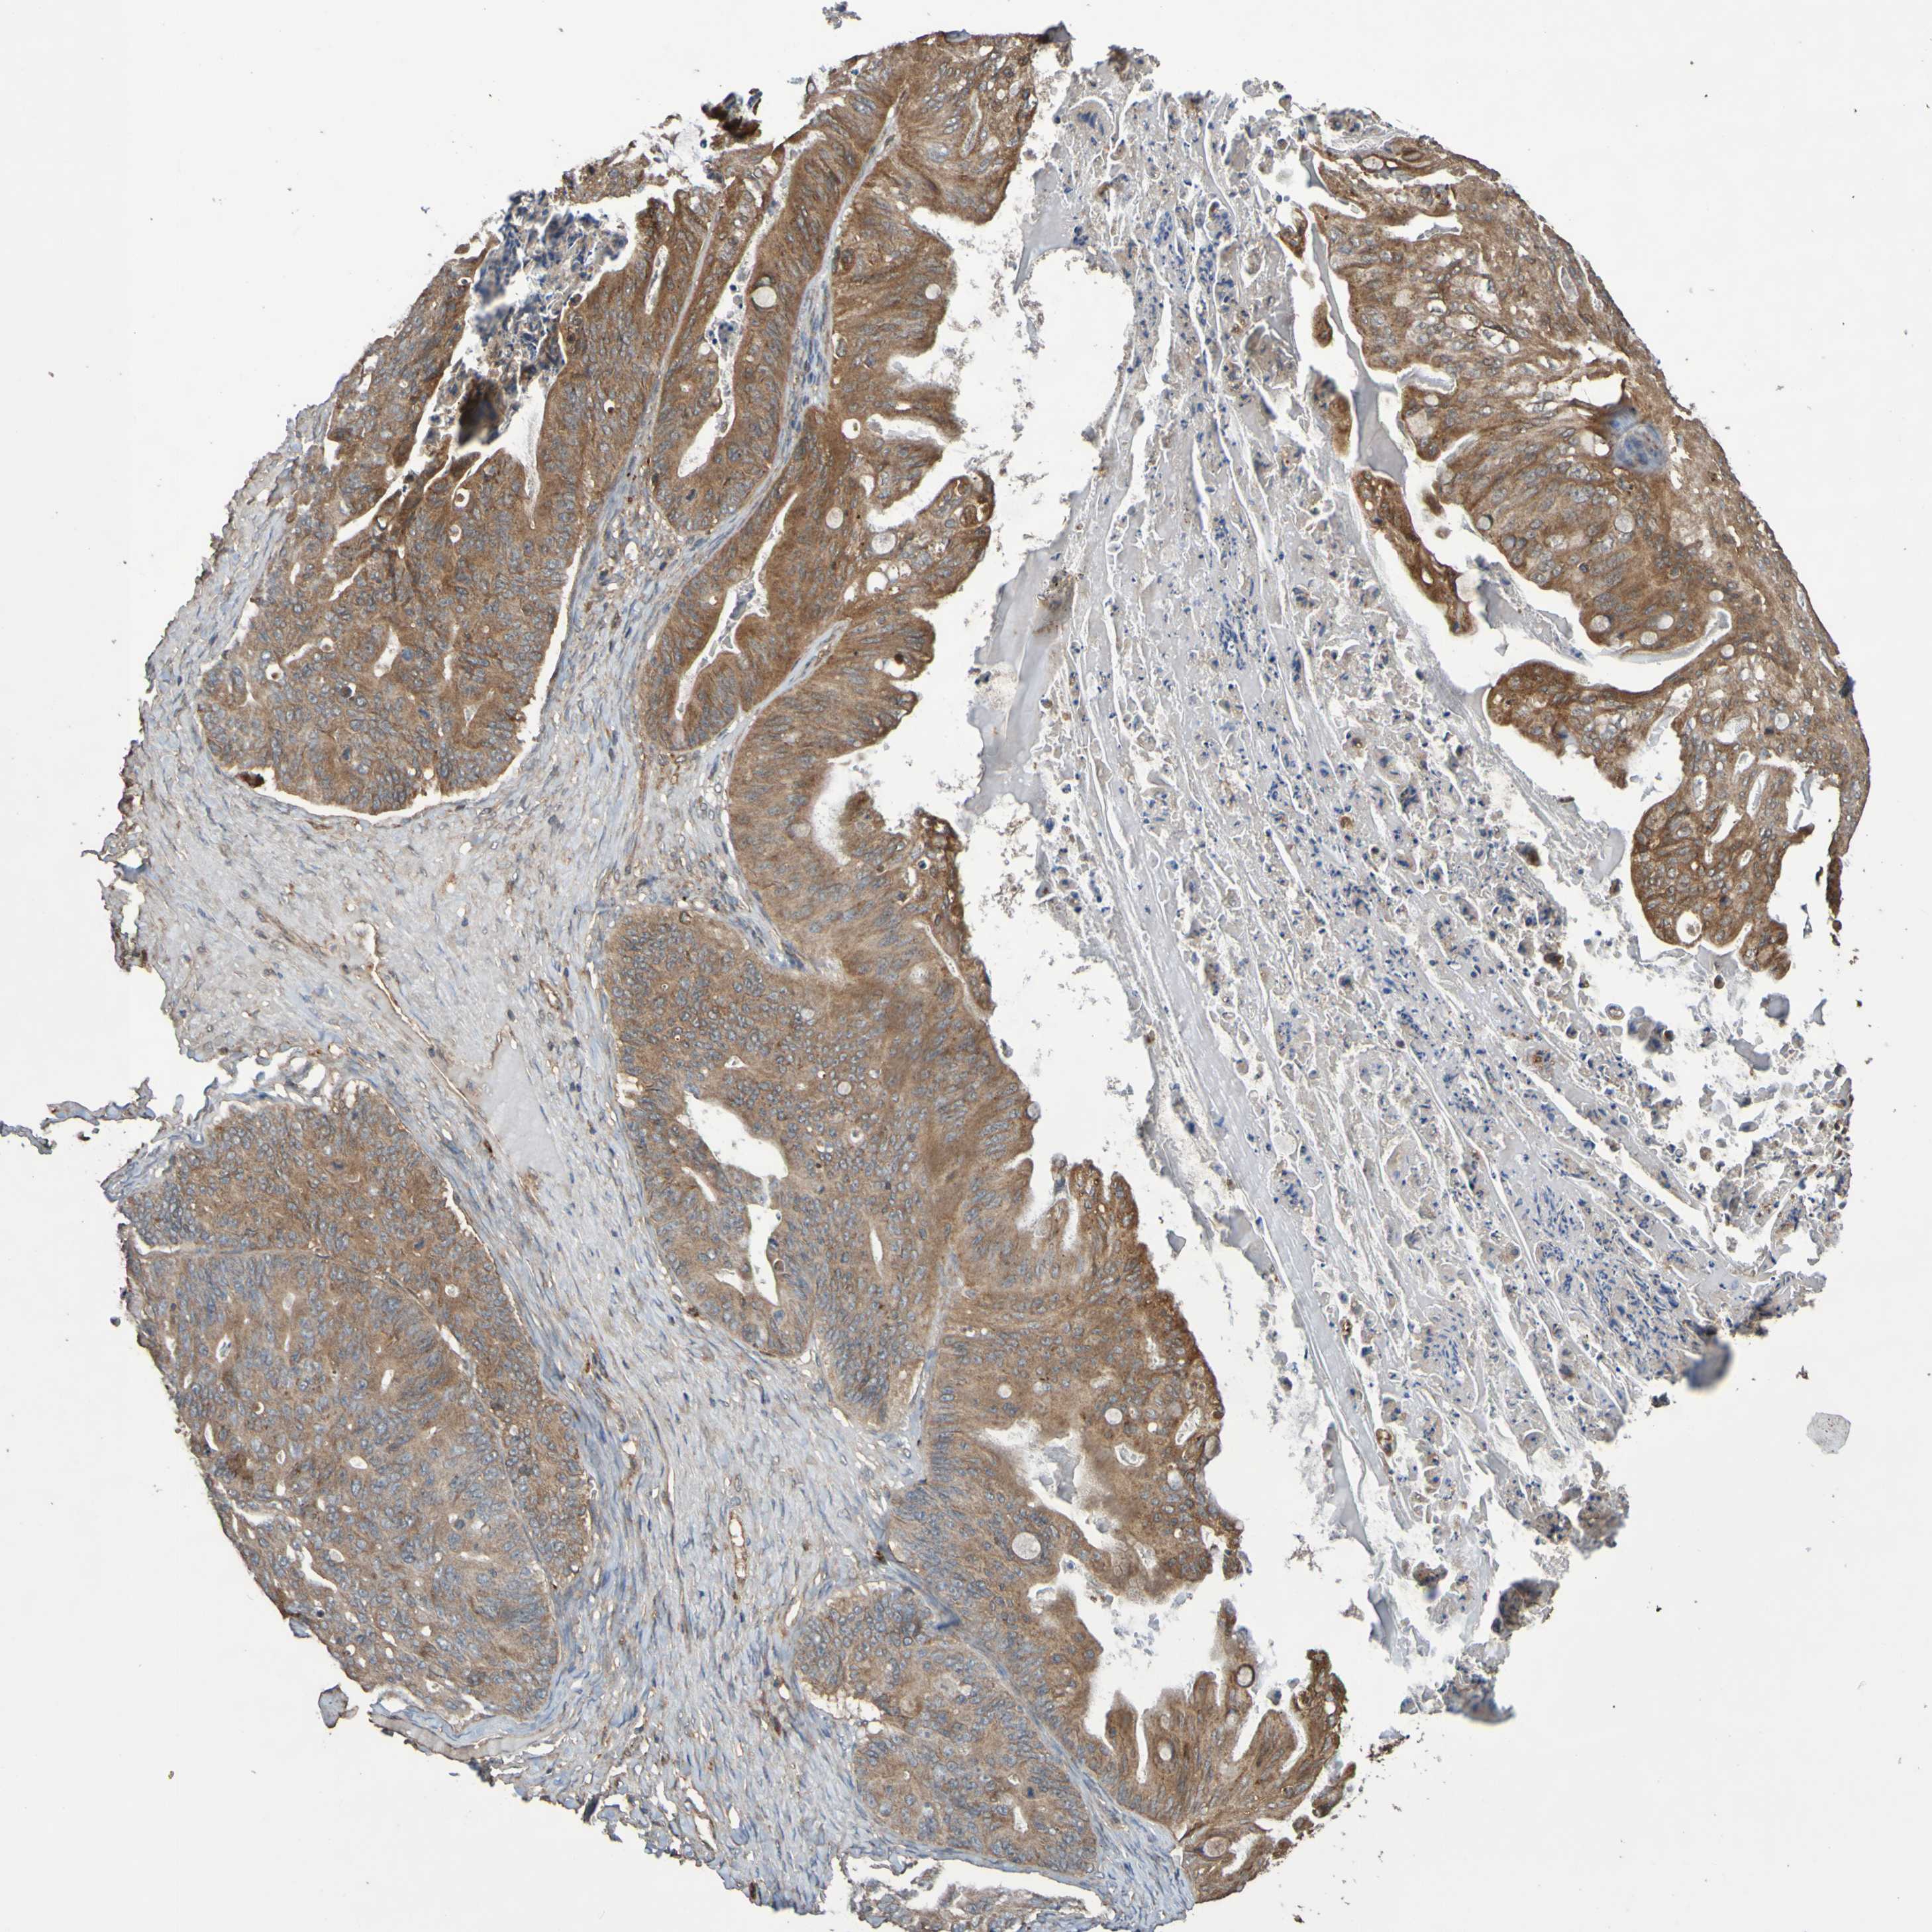

OVARIAN CANCER - Protein expressioni

A mouse-over function shows sample information and annotation data. Click on an image to view it in a full screen mode. Samples can be filtered based on level of antibody staining by selecting one or several of the following categories: high, medium, low and not detected. The assay and annotation is described here.

Note that samples used for immunohistochemistry by the Human Protein Atlas do not correspond to samples in the TCGA dataset.

Antibody stainingi

Antibody staining in the annotated cell types in the current human tissue is reported as not detected, low, medium, or high, based on conventional immunohistochemistry profiling in selected tissues. This score is based on the combination of the staining intensity and fraction of stained cells.

Each image is clickable and will lead to virtual microscopy that enables deeper exploration of all samples and also displays staining intensity scores, fraction scores and subcellular localization as well as patient and tissue information for each sample.

Antibody CAB010911

Staining

High

Medium

Low

Not detected

Intensity

Strong

Moderate

Weak

Negative

Quantity

>75%

75%-25%

<25%

None

Location

Nuclear

Cytoplasmic/membranous

Cytoplasmic/membranous,nuclear

Cystadenocarcinoma, serous, NOS

Carcinoma, endometroid

Cystadenocarcinoma, mucinous, NOS

Carcinoma, NOS